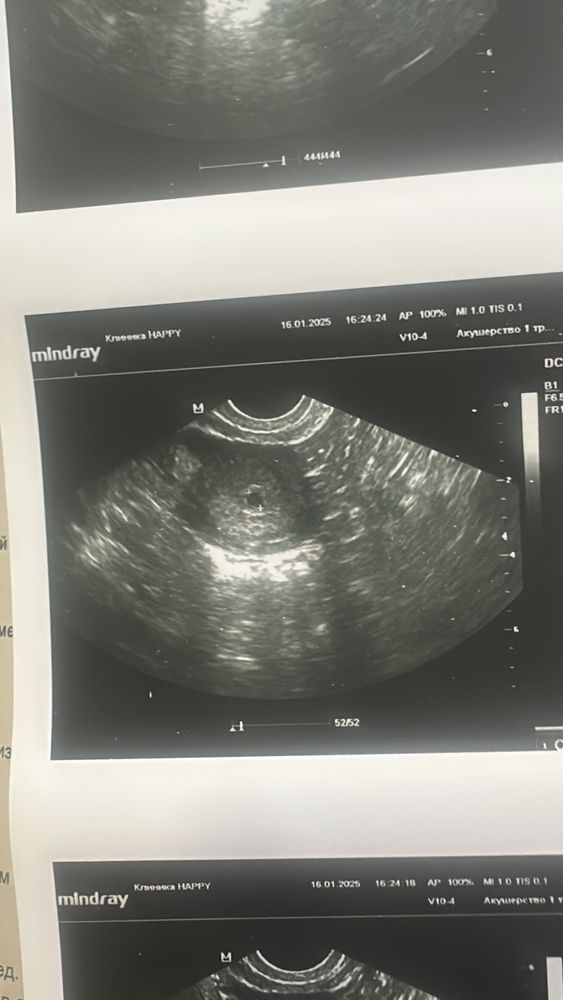

Первое узи

Даша, это по узи ставили 4 недели, акушерских было 5,4, пя был 6 мм